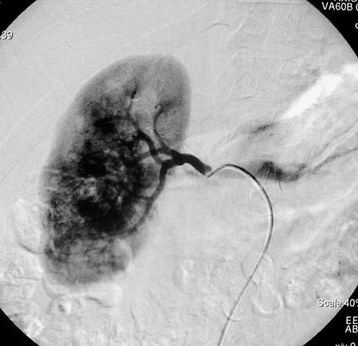

Obrázek 1 - angiografie pravé ledviny před léčbou s výraznou maligní vakularizací

V první fázi výkonu provádíme přehlednou diagnostickou angiografii abdominální aorty a selektivní nástřik renální tepny k posouzení cévního zásobení postižené ledviny (časté jsou varianty v počtu zásobujících tepen).